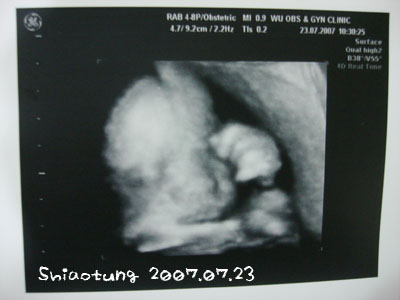

今天出門前,

我一樣拜託靚靚把正面轉過來,

不過顯然還是沒有多聽話,

我們都是很努力的趁她手移開的瞬間拍照片。

長肉了、長肉了!

這樣很像在睡覺,

其實她可動得咧!!

醫生說她在玩超人拳,

還說她什麼拳都會打喔!

手舞足蹈的...

連照超音波我的肚子都一直被踢。

這張臉胖嘟嘟,

注住的很可愛,

最後一張照片已經不想露臉了,

醫生說:妹妹,手走開喔,要收工囉!

但是左手還是遮臉,

於是就拍了這張,

醫生又說:還好不是比中指。